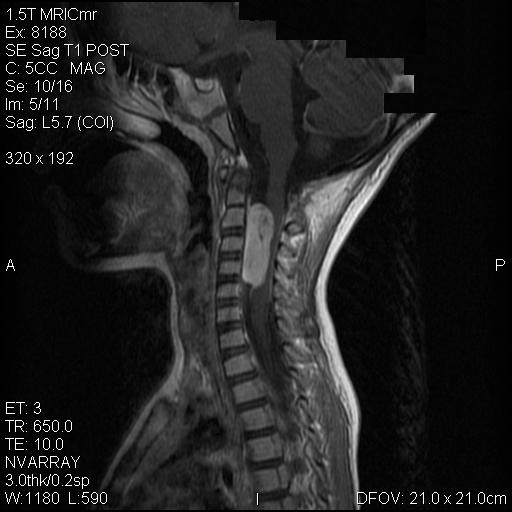

On T1-weighed images, the lesion appeared as a sausage-shaped mass that runs along the long axis of anterior portion of a spinal canal with marked compression of the spinal cord. The mass is well defined from the spinal cord and suggest an intradural, extramedullary location (Panel A). The mass abuts and slightly displaces the left vertebral artery forward. While the intracanalicular portion of the mass is well marginated, the anterolateral, extracanalicular component shows mild infiltration of the musculature. There is slightly heterogeneous enhancement of the mass. Some dural tail enhancement is also present (Panel B). On axial plane, extension of the mass through neuroforamens is well demonstrated (Panel C).

The main differential consideration was nerve sheath tumor. The seemingly rapid progression of the mass is highly suggestive of a high grade tumor. As no lesions are depicted in the brain, the possibility of a drop metastasis of ependymoma, medulloblastoma, supratentorial primitive neuroectodermal tumor (PNET), atypical teratoid rhabdoid tumor (AT/RT), and choroid plexus carcinoma is unlikely. The possibility for a metastatic carcinoma seems remote in this age. There is also a lack of evidence suggesting a metastatic neuroblastoma or hemopoietic neoplasm.